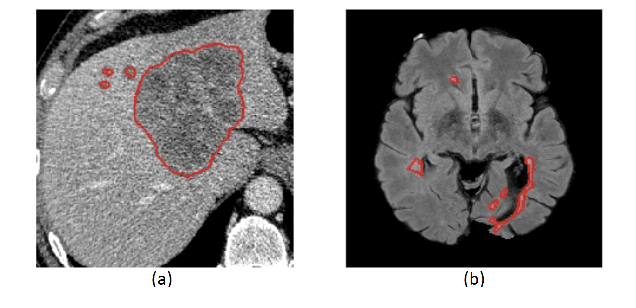

Abstract:Segmentation of anatomical regions of interest such as vessels or small lesions in medical images is still a difficult problem that is often tackled with manual input by an expert. One of the major challenges for this task is that the appearance of foreground (positive) regions can be similar to background (negative) regions. As a result, many automatic segmentation algorithms tend to exhibit asymmetric errors, typically producing more false positives than false negatives. In this paper, we aim to leverage this asymmetry and train a diverse ensemble of models with very high recall, while sacrificing their precision. Our core idea is straightforward: A diverse ensemble of low precision and high recall models are likely to make different false positive errors (classifying background as foreground in different parts of the image), but the true positives will tend to be consistent. Thus, in aggregate the false positive errors will cancel out, yielding high performance for the ensemble. Our strategy is general and can be applied with any segmentation model. In three different applications (carotid artery segmentation in a neck CT angiography, myocardium segmentation in a cardiovascular MRI and multiple sclerosis lesion segmentation in a brain MRI), we show how the proposed approach can significantly boost the performance of a baseline segmentation method.